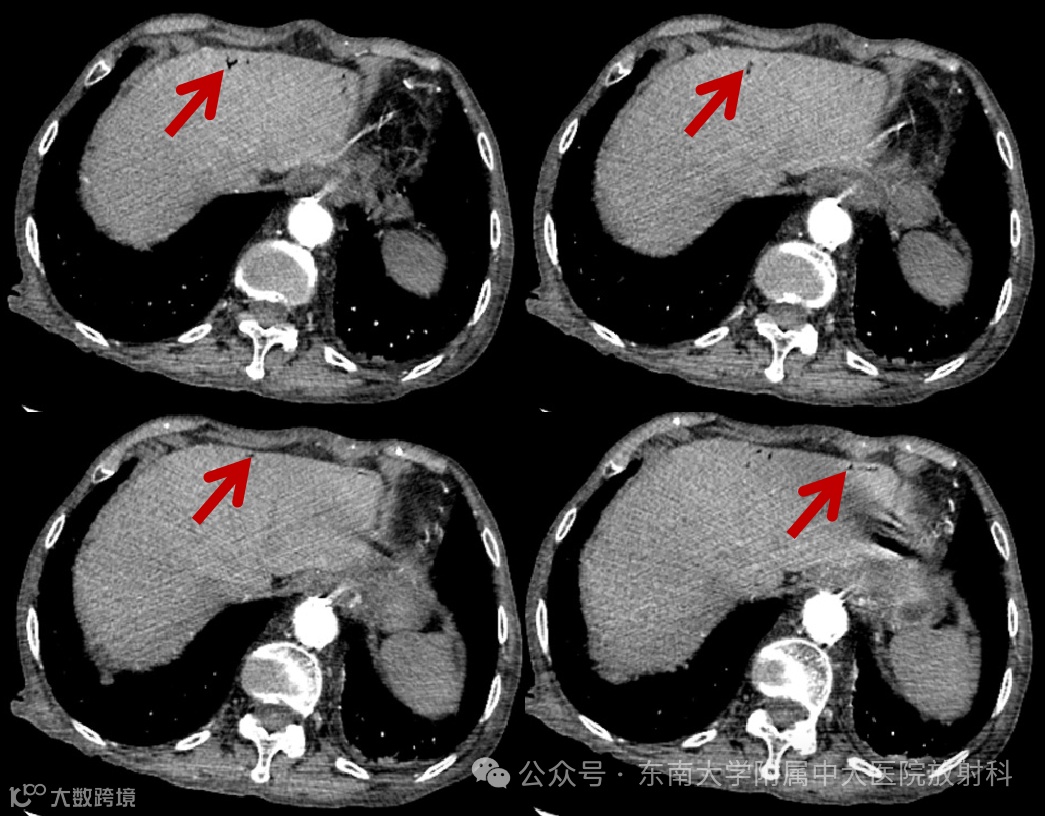

性别:女 年龄:84岁 -

主诉:因“全腹痛 2 天”入院 -

自诉腹痛难以忍受,伴腹胀、有压痛、反跳痛,伴恶心,休息未缓解。患者排气、排便减少

影像学表现